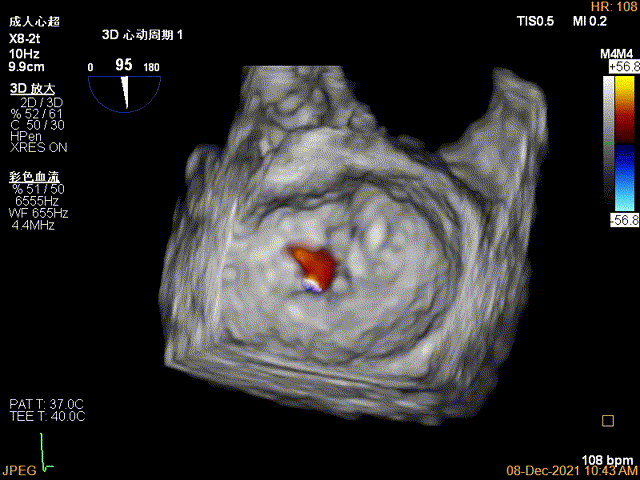

夹子关闭过程中,Color提示2区反流逐渐减少,残余反流位于夹子外侧

第一个夹子放置侯二尖瓣口平均跨瓣压差:4mmHg